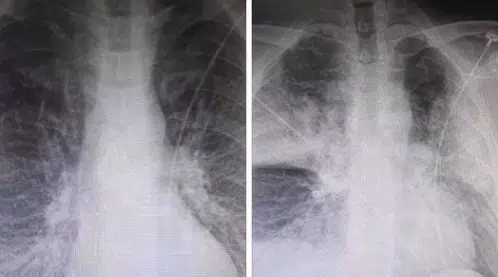

Οι δύο ακτινογραφίες, που ανήρτησε στο Facebook ακτινολόγος από το ΚΑΤ, προκαλούν σοκ, καθώς σε αυτές αποτυπώνεται η ραγδαία επιδείνωση που προκαλεί ο κορωνοϊός στους ασθενείς.

Ειδικότερα, ο κ. Μάνος Καρράς σημειώνει ότι οι δύο ακτινογραφίες ενός 38χρονου, ο οποίος είναι καπνιστης και διαβητικός, έχουν καταγραφεί με 7,5 ώρες διαφορά.

Η πρώτη είναι από την εισαγωγή ασθενή στις 12 το μεσημέρι με 98% κορεσμό οξυγόνου και η δεύτερη, η επαναληπτική, πραγματοποιήθηκε στις 19:30 με τον ασθενή να είναι πλέον με μάσκα οξυγόνου.

Σύμφωνα με τον κ. Καρρά τα «σύννεφα» στη δεύτερη ακτινογραφιά συνήθως σημαίνουν υγρό οίδημα φλεγμονή και «είναι κομμάτι του πνεύμονα που “δεν αναπνέει”».